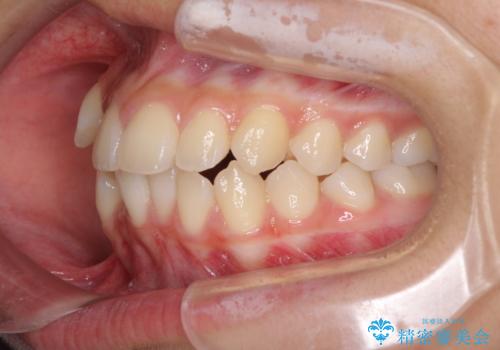

- 前歯のデコボコと八重歯を気にして来院された患者様です。

本人はあまり実感はありませんでしたが、同席されたご家族より口がすぐに開いてしまうことを指摘されていました。

口元に力の入る歯列であったため、上顎左右第一小臼歯4本を抜歯するワイヤー矯正を行うこととしました。

当初は八重歯やデコボコが一番気になっていましたが、抜歯矯正により口元の突出感が改善されるにつれ、口の閉じやすさを実感するようになってきました。